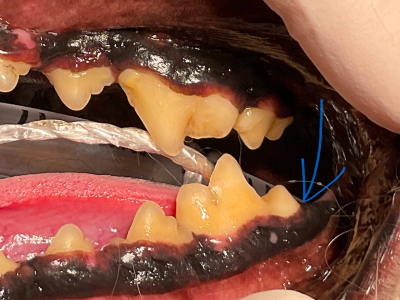

術前

見ためはとてもきれいで正常に見えますが…

治療前X線

X線を撮ってみると歯の後ろ側の骨が歯周病によりなくなっています。